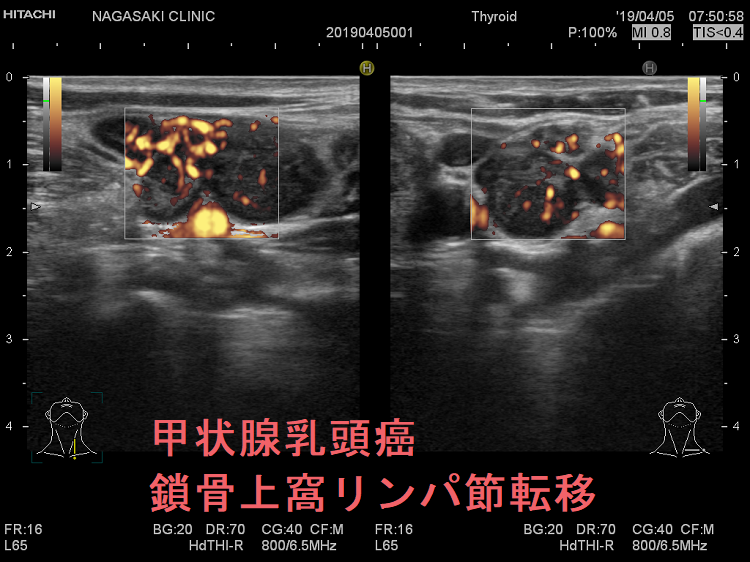

甲状腺乳頭癌の鎖骨上窩リンパ節転移再発

甲状腺乳頭癌鎖骨上窩リンパ節転移再発

甲状腺乳頭癌の鎖骨上窩リンパ節転移再発 超音波(エコー)画像

鎖骨上窩は予防的リンパ節郭清(前頚部リンパ節郭清)の範囲外につき、術後リンパ節再発のピットフォールとなります(意外とよく見つかります)。

甲状腺乳頭癌 鎖骨上窩リンパ節転移 超音波(エコー)画像

甲状腺乳頭癌 左鎖骨上窩リンパ節転移 超音波(エコー)画像;いびつな形で、周囲との境界が一部不明瞭化して浸潤が疑われる。リンパ門は消失し、砂粒状石灰化が著明

甲状腺乳頭癌 鎖骨上窩リンパ節転移 超音波(エコー)画像 ドプラーモード

甲状腺乳頭癌 左鎖骨上窩リンパ節転移 超音波(エコー)画像 ドプラーモード;内部に異常な走行の血管を認め、血流豊富。